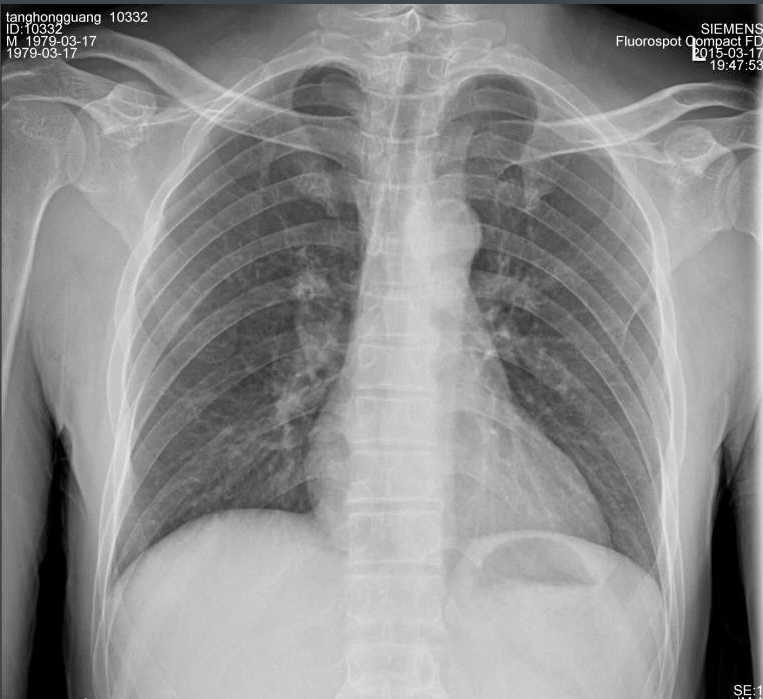

X射線因其波長短,能量大,照在物質上時,僅一部分被物質所吸收,大部分經由原子間隙而透過,表現出很強的穿透能力。X射線穿透物質的能力與X射線光子的能量有關,X射線的波長越短,光子的能量越大,穿透力越強。X射線的穿透力也與物質密度有關,利用差別吸收這種性質可以把密度不同的物質區分開來 。

X射線同可見光一樣能使膠片感光。膠片感光的強弱與X射線量成正比,當X射線通過人體時,因人體各組織的密度不同,對X射線量的吸收不同,膠片上所獲得的感光度不同,從而獲得X射線的影像 。